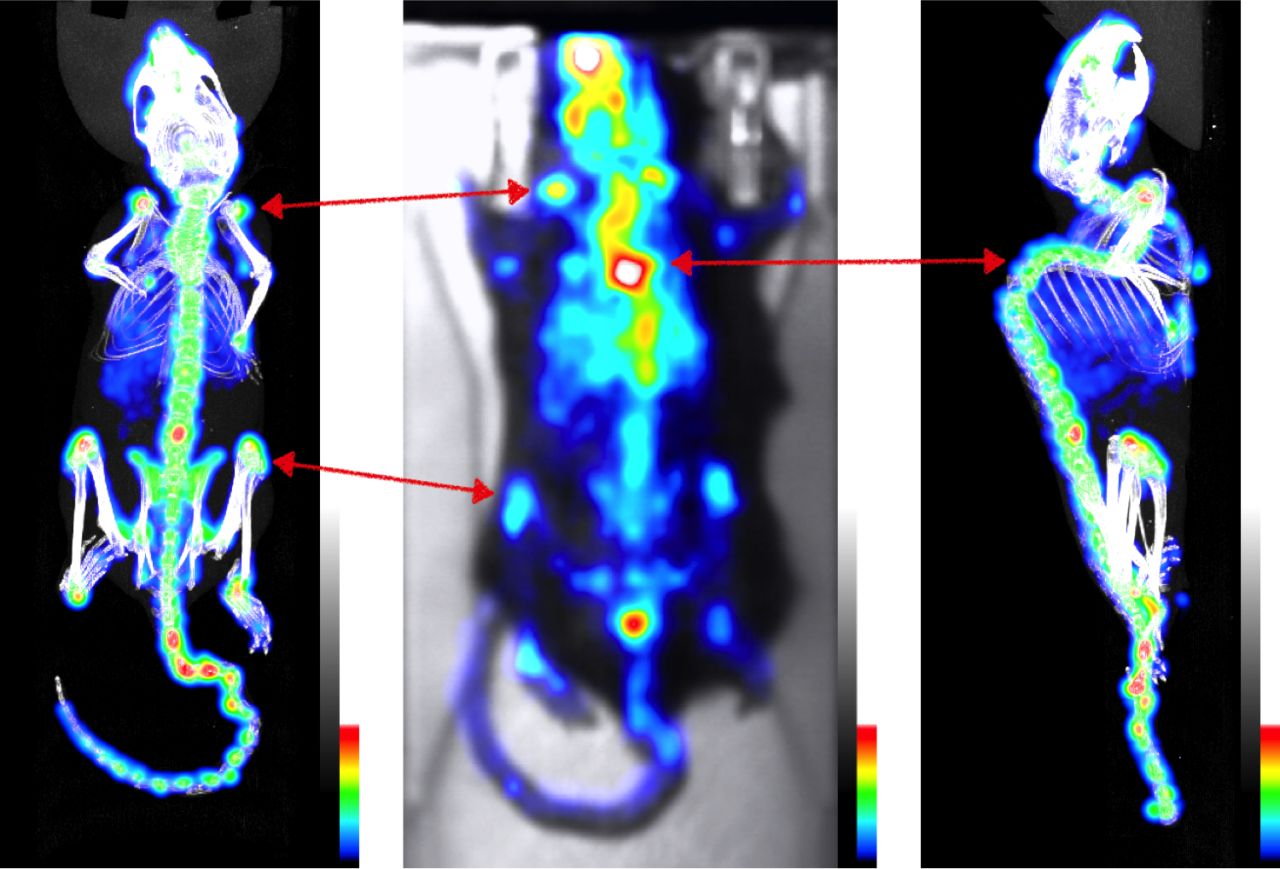

This week in BIOEMTECH Laboratories & in collaboration with our good partners from Biomedcode, we are setting up a pre-clinical platform for the diagnosis and therapy of Spondyloarthritis, within the SEPIA National Project scope. Mice were imaged with 99mTc-MDP and pathology regions are highlighted both on planar dynamic imaging with γ-eye (BIOEMTECH) and in tomographic scans with γ-CUBE (MOLECUBES).